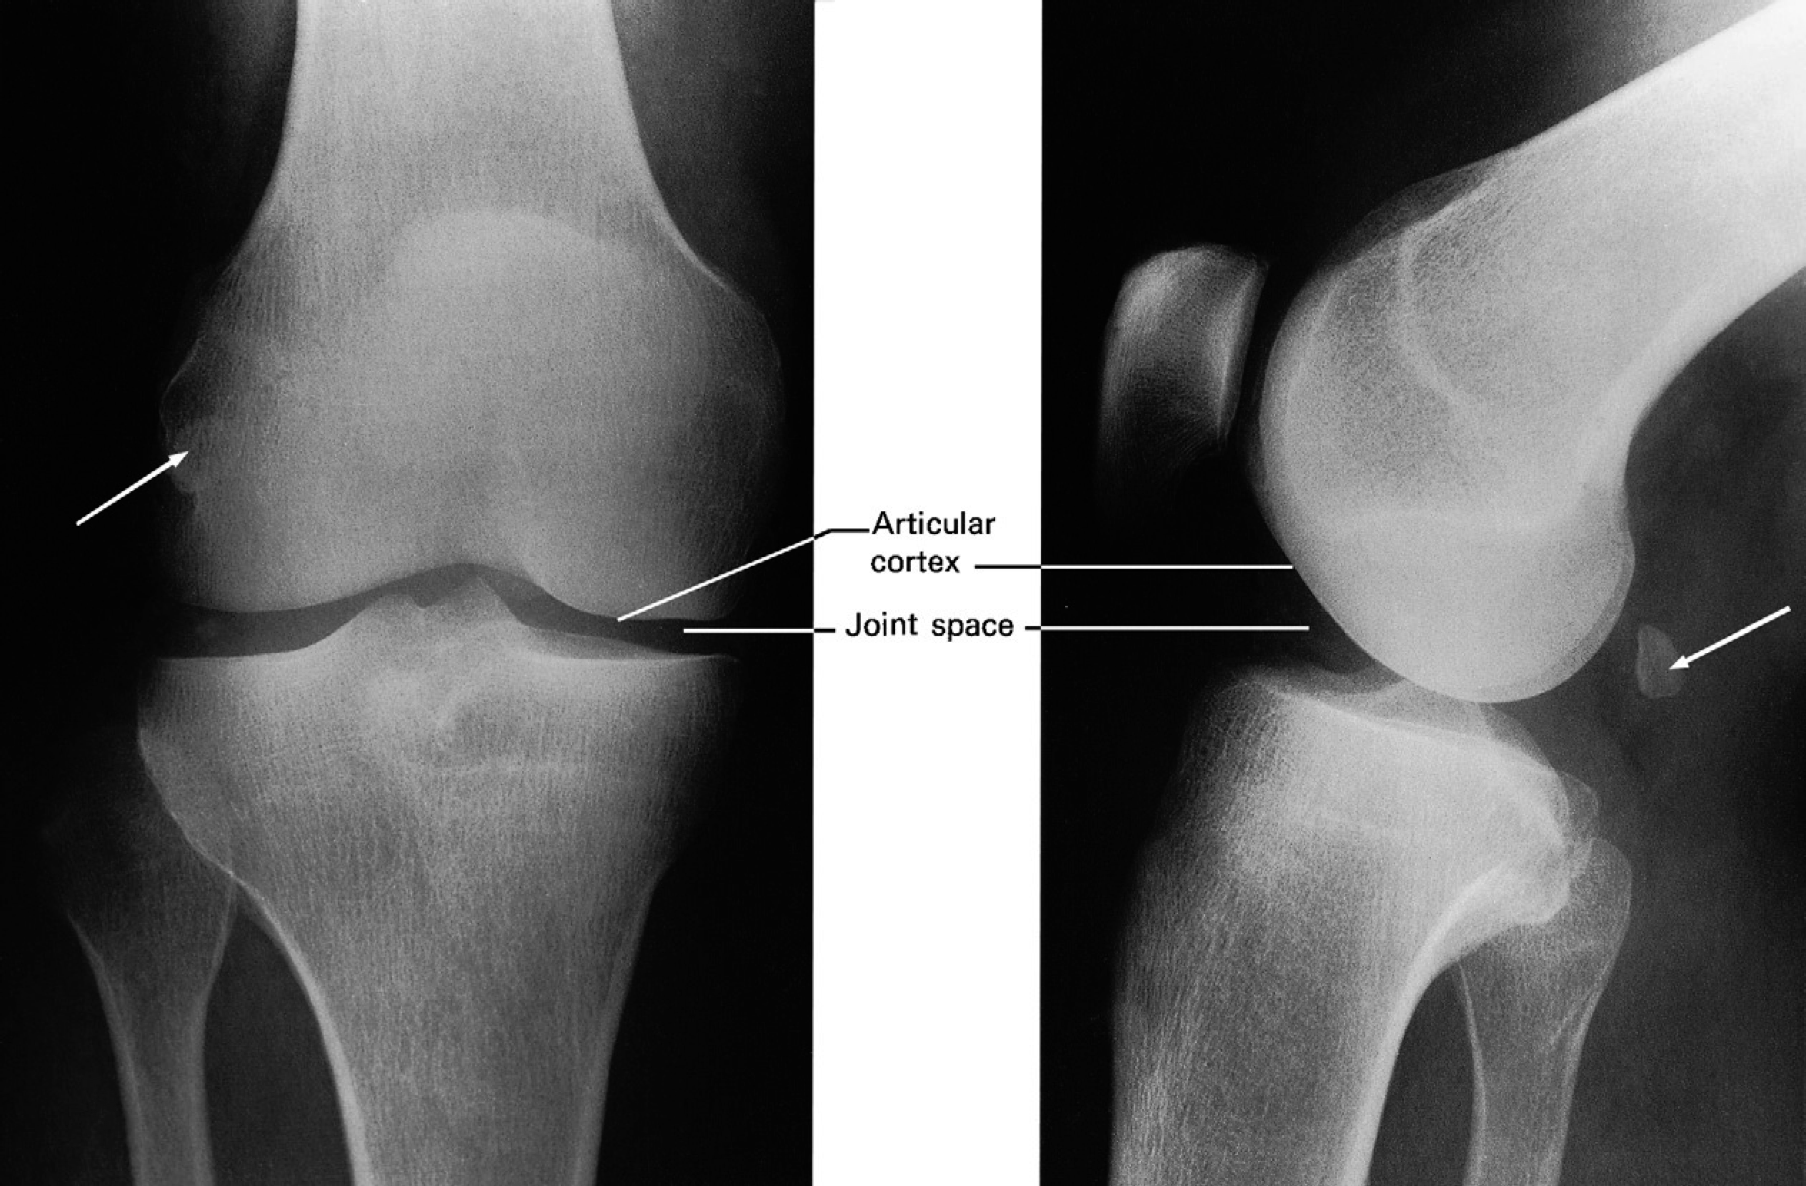

Normal knee joint. Note the fabella (arrow), a sesamoid bone in the gastrocnemius. The ‘joint space’ consists of articular cartilage and synovial fluid.